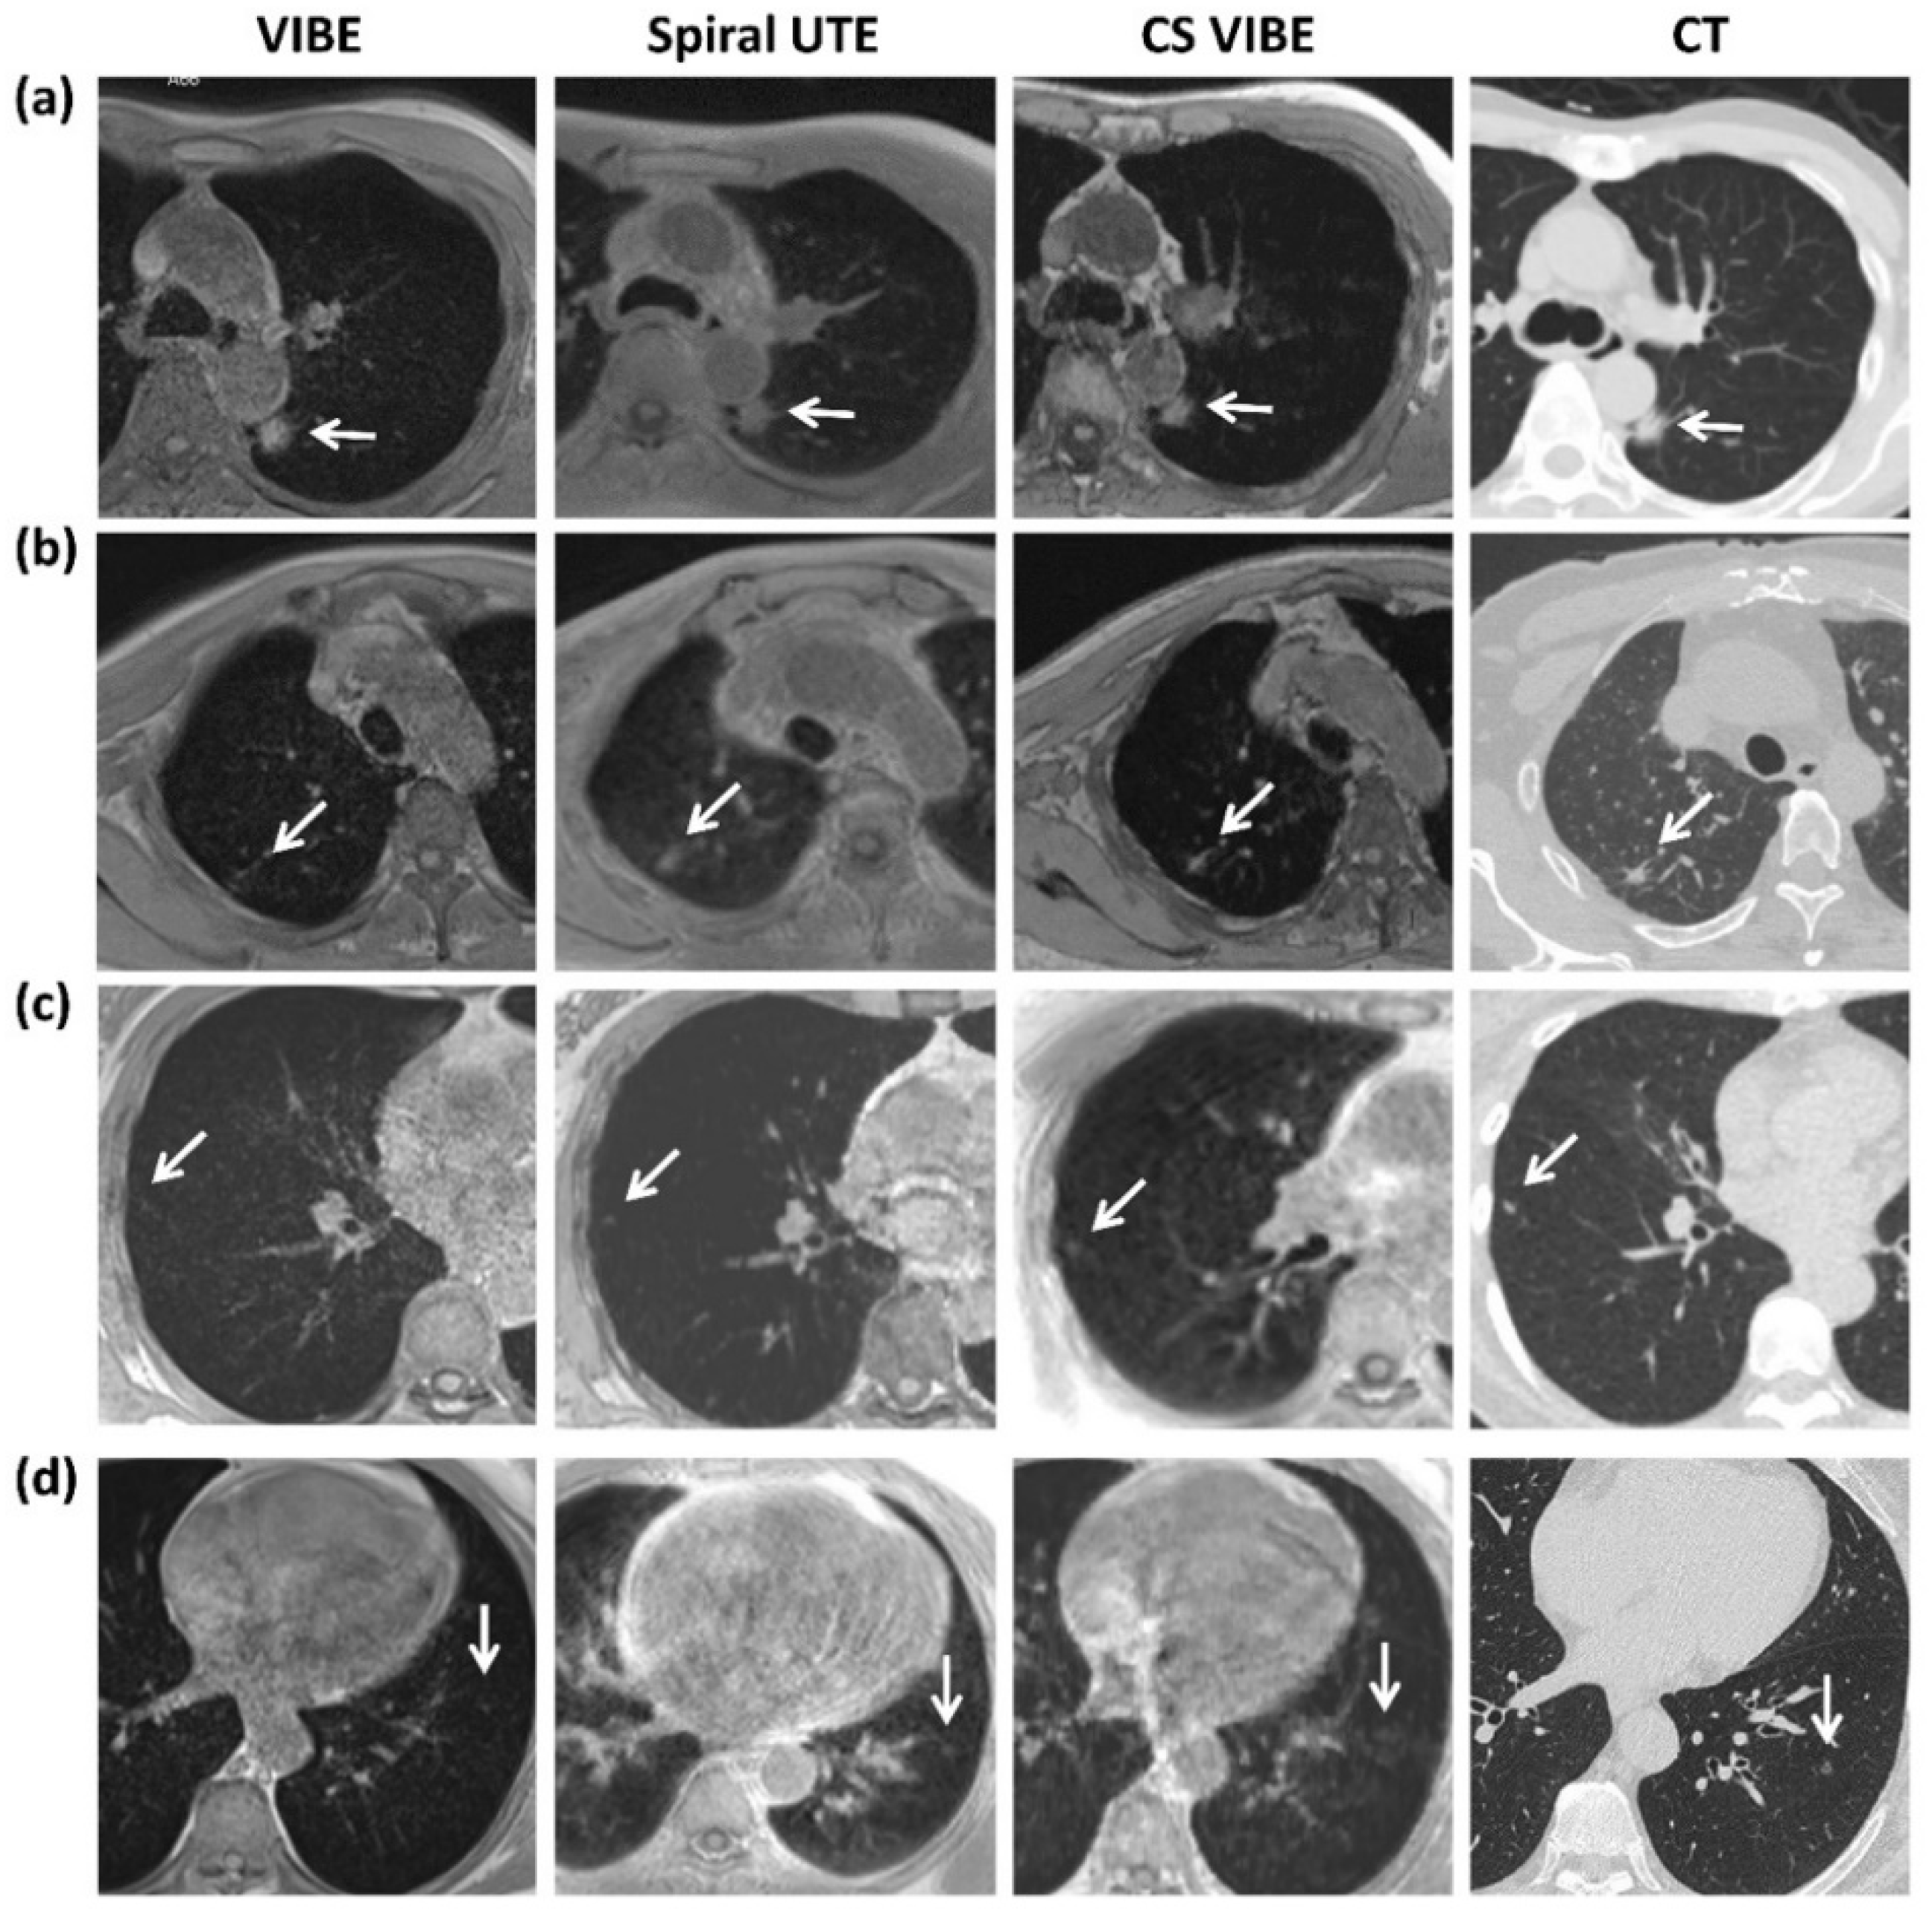

- Both UTE and CS-VIBE sequences provide radiation-free pulmonary nodule detection, which is suitable for young people, pregnant women, patients requiring serial and longitudinal follow-up, or people unwilling to undergo radiation exposure.

- Variable respiratory motion management (breath-hold for CS-VIBE with scanning durations of 13 s vs. free-breathing for spiral UTE with scanning durations of 3.5–5 min) was investigated.